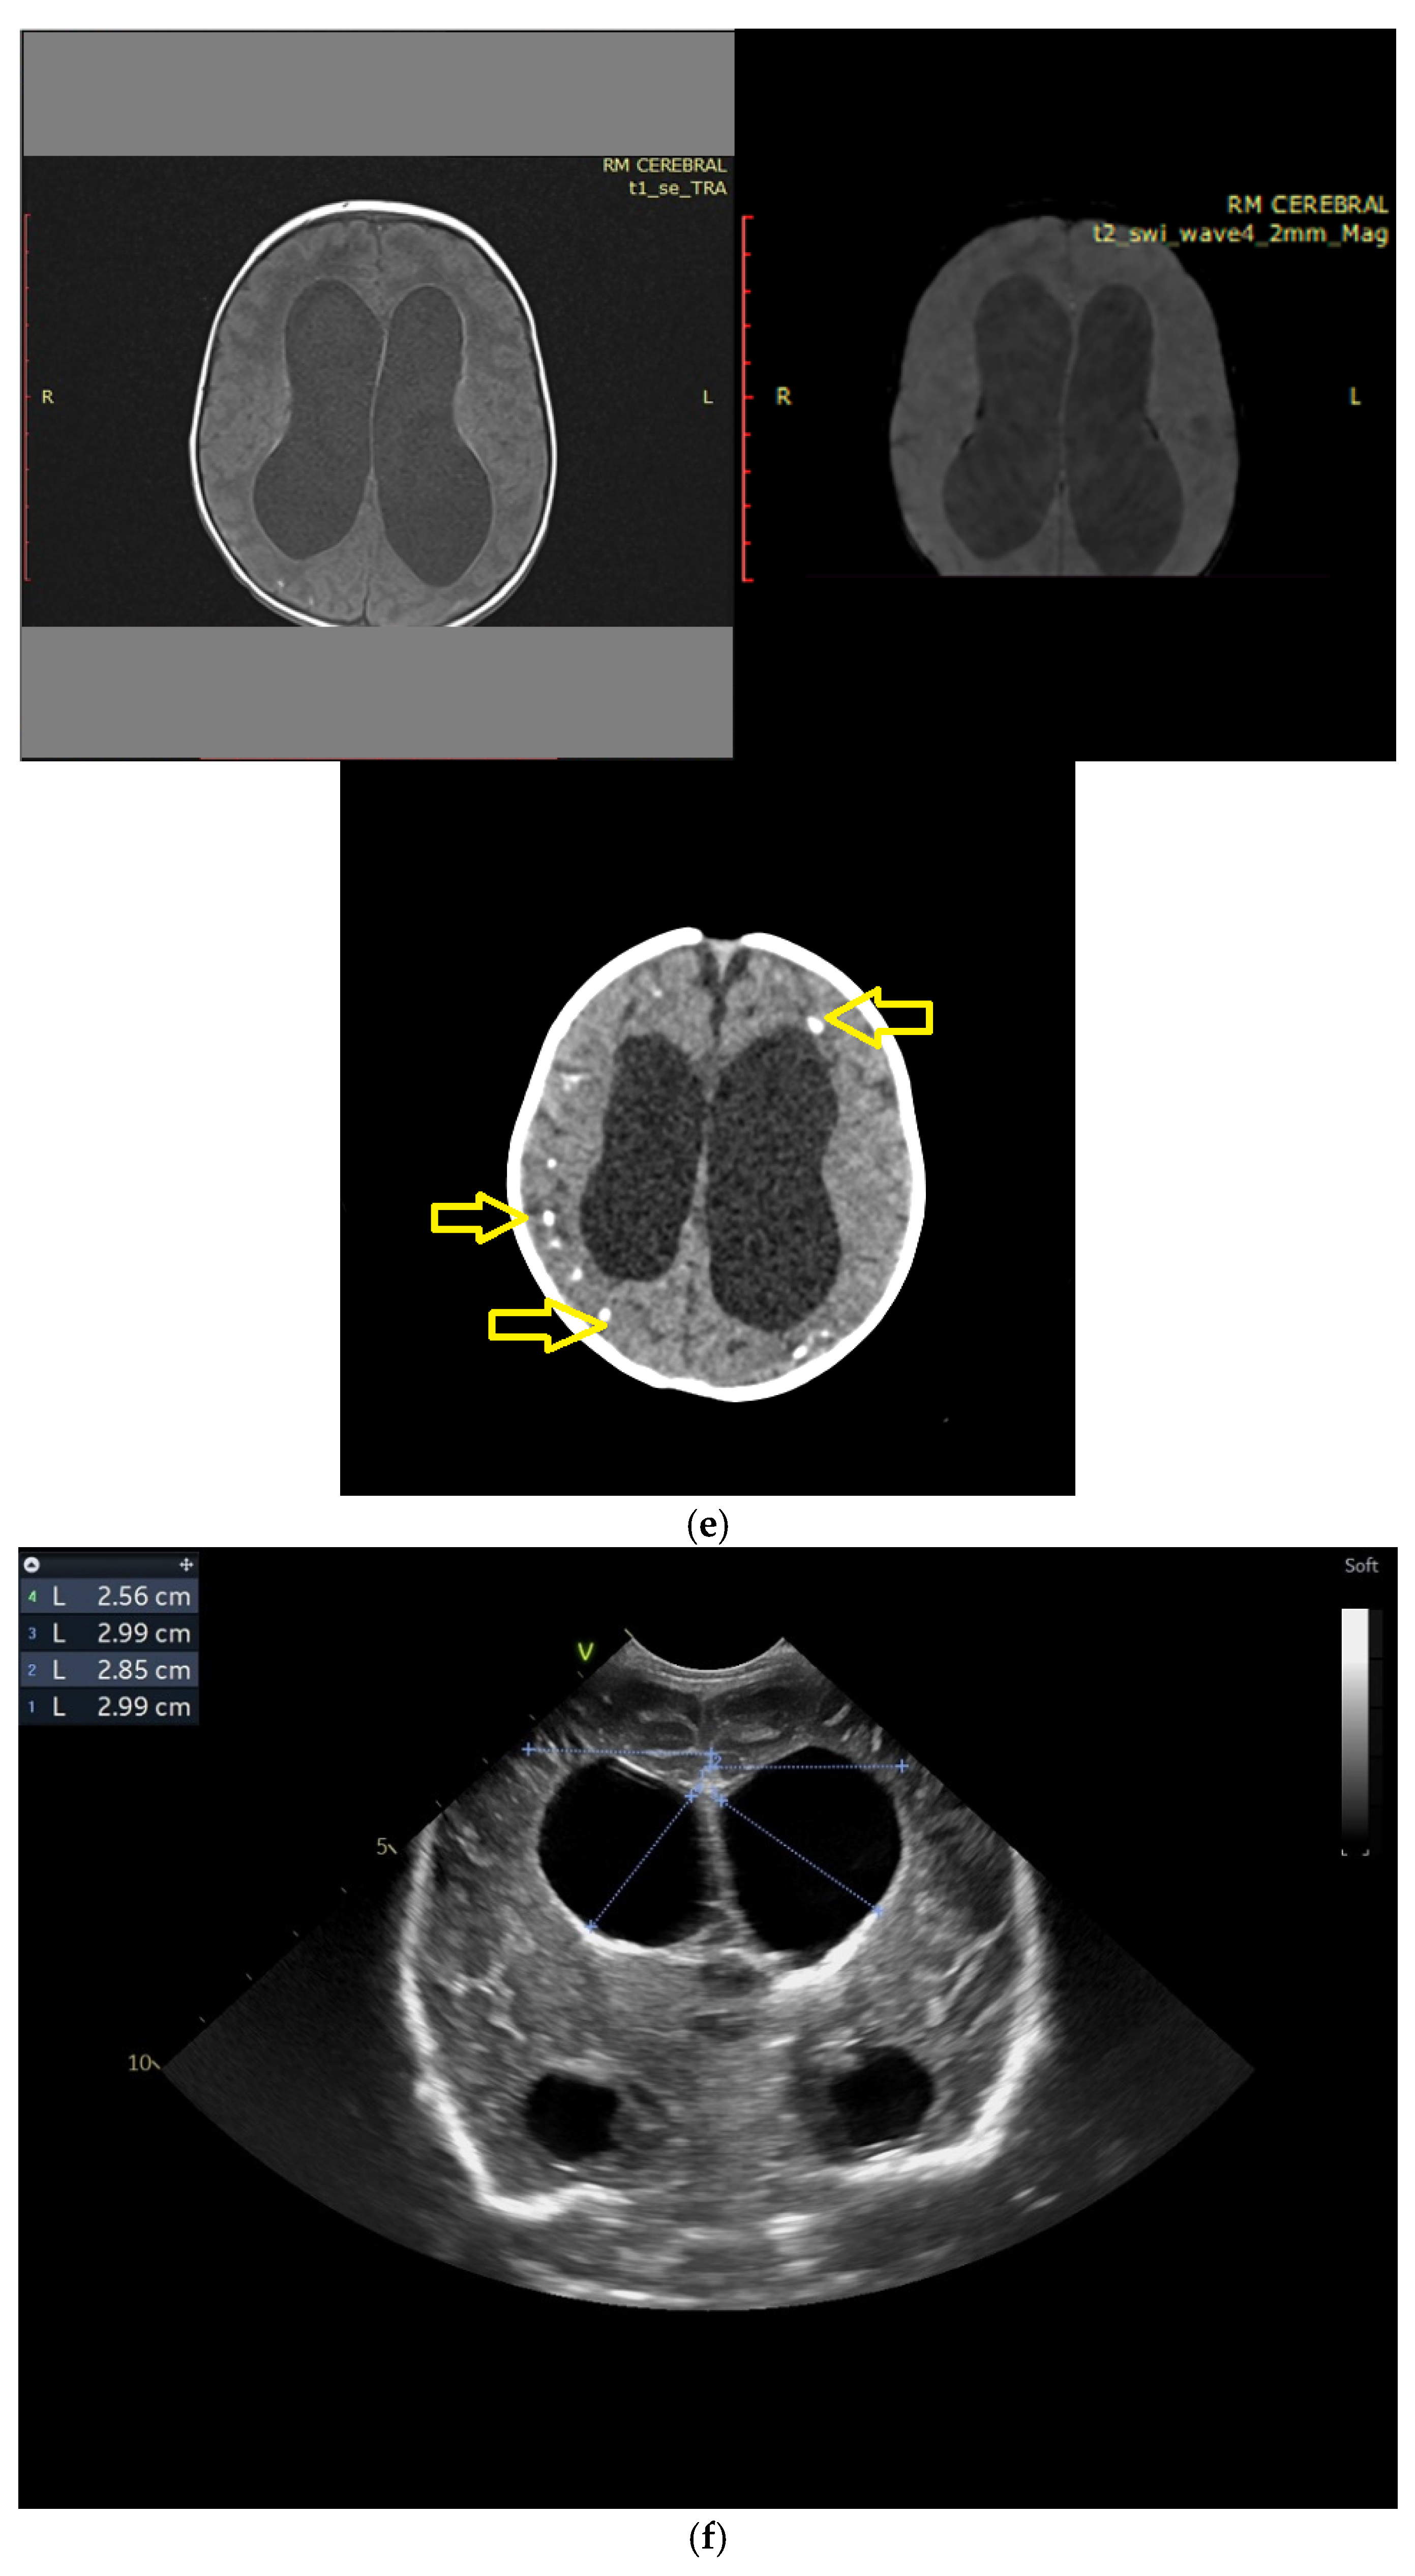

Figure 4.

(a) Cranial ultrasound. Coronal view. Lateral ventricles and third ventricle enlargement. L1, L2—Levine index measurement. L3, L4—posterior horn of the lateral ventricles’ width measurement. L5—third ventricle width measurement (personal image collection). (b) Cranial ultrasound. Sagittal view. Enlarged third and fourth ventricles. L1, L2—third ventricle measurements. L3, L4—fourth ventricle measurements (personal image collection). (c) Cranial ultrasound. Sagittal view. Enlarged lateral ventricles. Up—left ventricle. Down—right ventricle (personal image collection). (d) Cranial ultrasound. Coronal view. Punctuate hyperechoic images were observed in the right lobe (personal image collection). (e). Up left—MRI T1 sequence. Up right—MRI T2 sequence—susceptibility weight imaging (SWI). Down—CT scan. Transversal view. Yellow arrows—multiple calcifications can be seen in the CT scan (personal image collection). (f) Cranial ultrasound. Coronal view. Lateral ventricles. L1, L2—Levine index measurement. L3, L4—anterior horn width measurement. Blue arrow—intraventricular shunt (personal image collection). (g) Cranial ultrasound. Sagittal view. Thalamo-occipital distance measurements. Up—right ventricle. Down—left ventricle (personal image collection).

At six weeks after birth, an MRI scan was performed, while a CT scan was performed at 14 weeks of life, both providing valuable information regarding the sequelae of Toxoplasmosis (Figure 4e). Even though a few signs were observed on the MRI, the CT scan better outlined the presence of the parenchymal calcifications. A neurosurgical intervention was intended, a ventricle puncture was performed, and a shunt was placed in the right ventricle. The cranial ultrasound at two months of life did not show notable improvements, however (Figure 4f,g). The neurological examinations showed axial hypotonia and limb hypertonia.